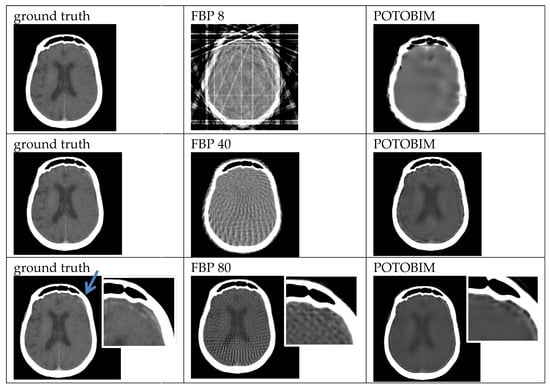

2.3. Sparse-View Reconstruction

3. Results

3.1. Visual Grading

3.2. Quantitative Evaluation